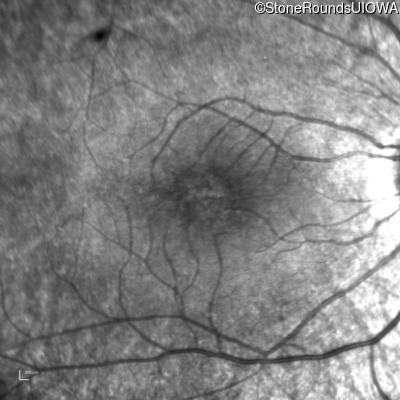

Infrared Fundus Photograph - Right - 20/32 -1

Exemplar